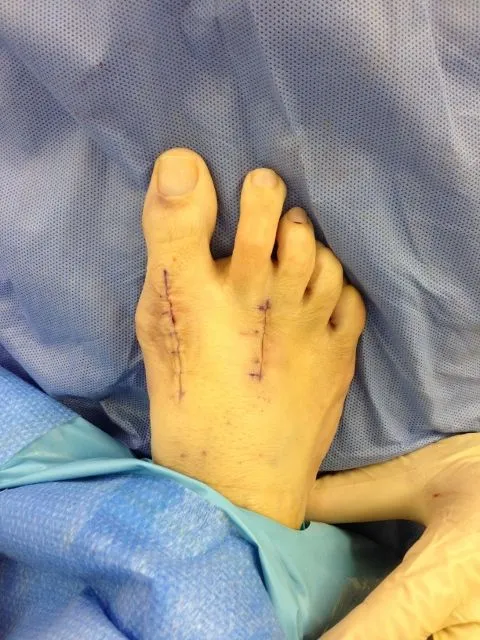

Intraop Pic Immediately After Correction

Immediate Postop in OR

During surgical correction of the bunion a v-shape bone is made in most cases to translate the head of the 1st metatarsal laterally which creates an overhang of bone from the previous position of the bone (pictured left). The overhang is remove and the new position of the bone is held with some type of fixation which varies from screws, staples, or pins which is the case here. The pin is buried left in permanently (pictured right).

Immediate post op pic